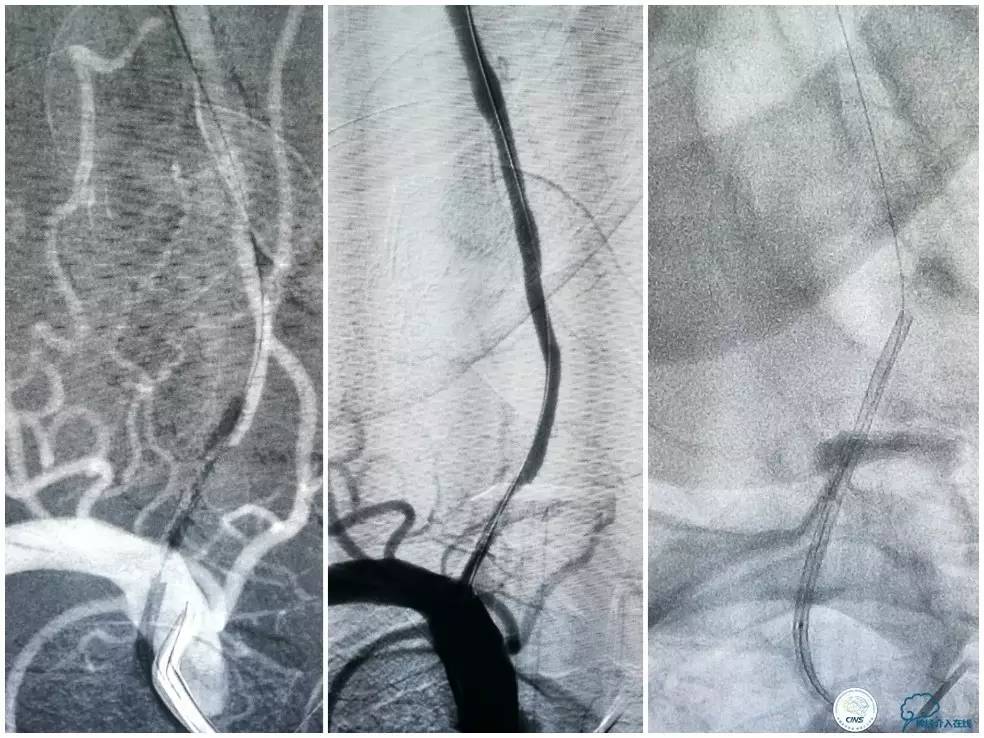

全麻下右侧股动脉穿刺置入8F动脉鞘,6F导引导管到位,送入Traxcess(0.014″200cm)微导丝+Echelon-10微导管谨慎通过右侧椎动脉V1段狭窄处至V2段远端,交换撤出Traxcess微导丝,送入Transend(0.014″300cm)微导丝至V2段远端(图10)。

图10

Ultra-Soft球囊(3.0mm×20mm)于狭窄处预扩张后置入EXCEL支架(4.0 mm× 24mm),球扩后造影见支架贴壁良好,远端血管显影好,前向血流TICI3级。6F导引导管沿微导丝通过右椎动脉V1段支架至V2段(图11)。

图11